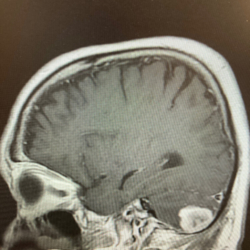

This X-ray shows the lump found in Stephan Bunker’s head two years ago. He is using his experience to inform other firefighters about carcinogens in the workplace. Submitted photo

Bunker was shown a picture of the scan which clearly showed he had a spot behind his right ear against his brain that shouldn’t be there. His PCP told Bunker he had good news and bad news. The bad news was it was fast growing and needed to come out immediately.